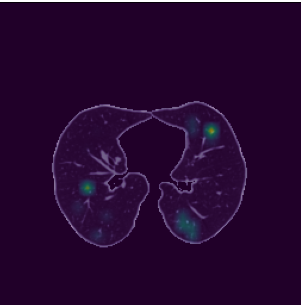

As mentioned before, CT-xCOV enriches the visualization’s explanations with the textual ones. We provide users with information on the degree of infection, which is calculated as the size of the infected region shown by a visualization method divided by the size of the lungs. Additionally, we provide the degree of infection per lung (i.e. right/left) to give more information about the most infected lung. Figure 8 shows an example of visual and textual explanations using the Grad-Cam method: the infected region is highlighted and the percentage of infection is computed.

Refer to caption

Figure 8: Percentage of infection in the lungs based on the explanation provided by Grad CAM; "Total degree of infection in both lungs: 10.98 %, 4.26 % in the left lung and 6.72 % in the right lung".